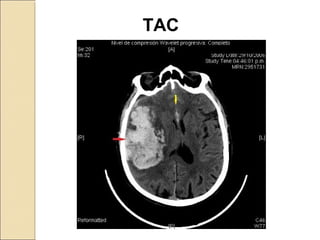

MÉTODOS DE ESTUDIO DEL CEREBROMÉTODOS DE ESTUDIO DEL CEREBRO

Técnicas de generación de imágenes:

Tomografía Axial Computarizada

TAC